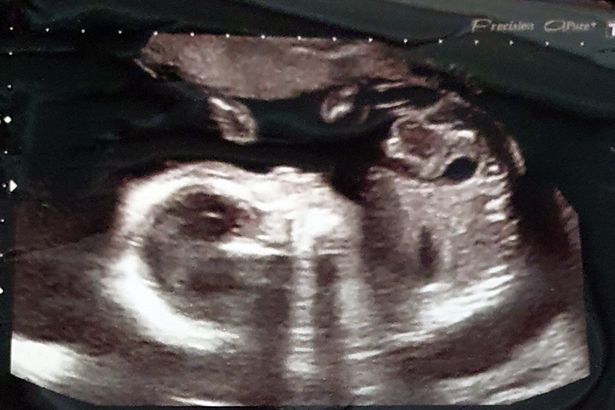

Alex’s scan was first discovered by doctors during his 20-week scan, confirmed reports. Therefore, during the first six months of his life, he was forced to undergo several medical tests as well as operations at Bristol’s Royal Hospital for Children.